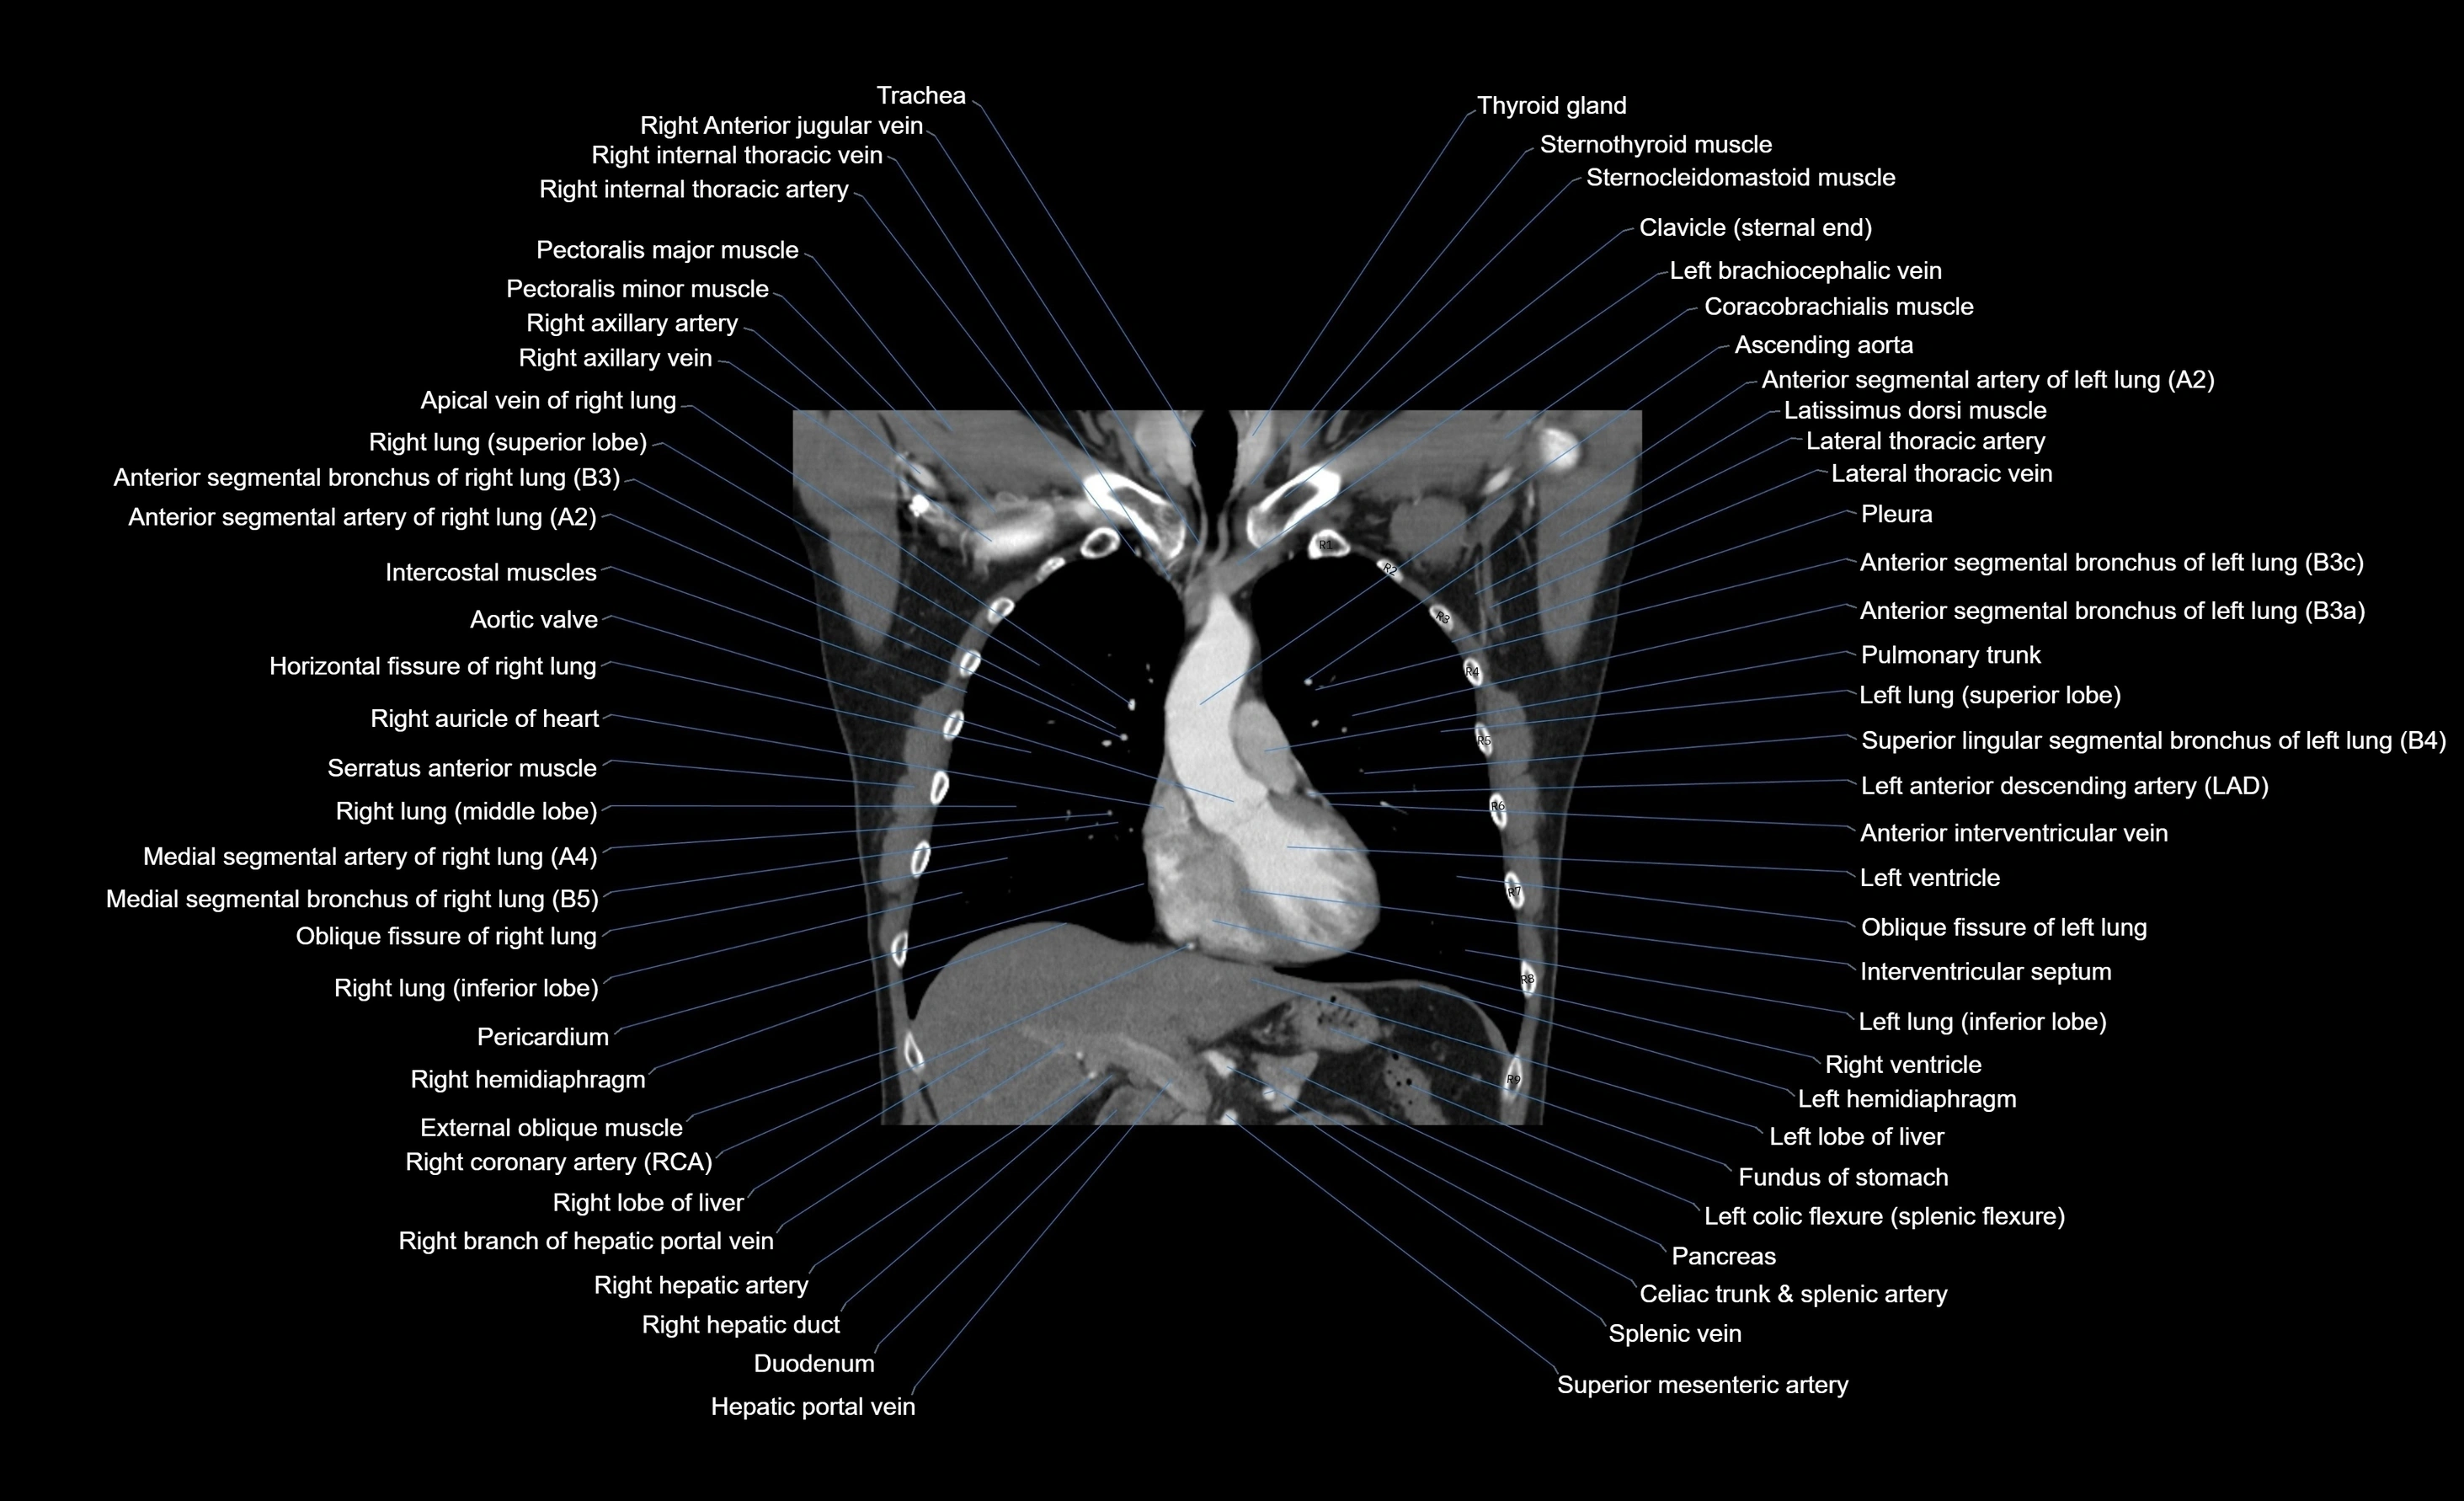

- Aortic valve

- Ascending aorta

- Brachiocephalic trunk

- Coracobrachialis muscle

- Duodenum – Superior part (D1)

- Hepatic portal vein

- Horizontal fissure of right lung

- Lateral thoracic artery

- Latissimus dorsi muscle

- Left anterior descending artery (LAD)

- Left brachiocephalic vein

- Left ventricle

- Pancreas

- Pulmonary trunk

- Right auricle of heart

- Right coronary artery (RCA)

- Right hepatic artery

- Right lobe of liver

- Right lung (inferior lobe)

- Right lung (middle lobe)

- Right lung (superior lobe)

- Right ventricle

- Serratus anterior muscle

- Spleen

- Splenic artery

- Splenic vein

- Superior mesenteric artery (SMA)

- Thyroid gland

- Trachea